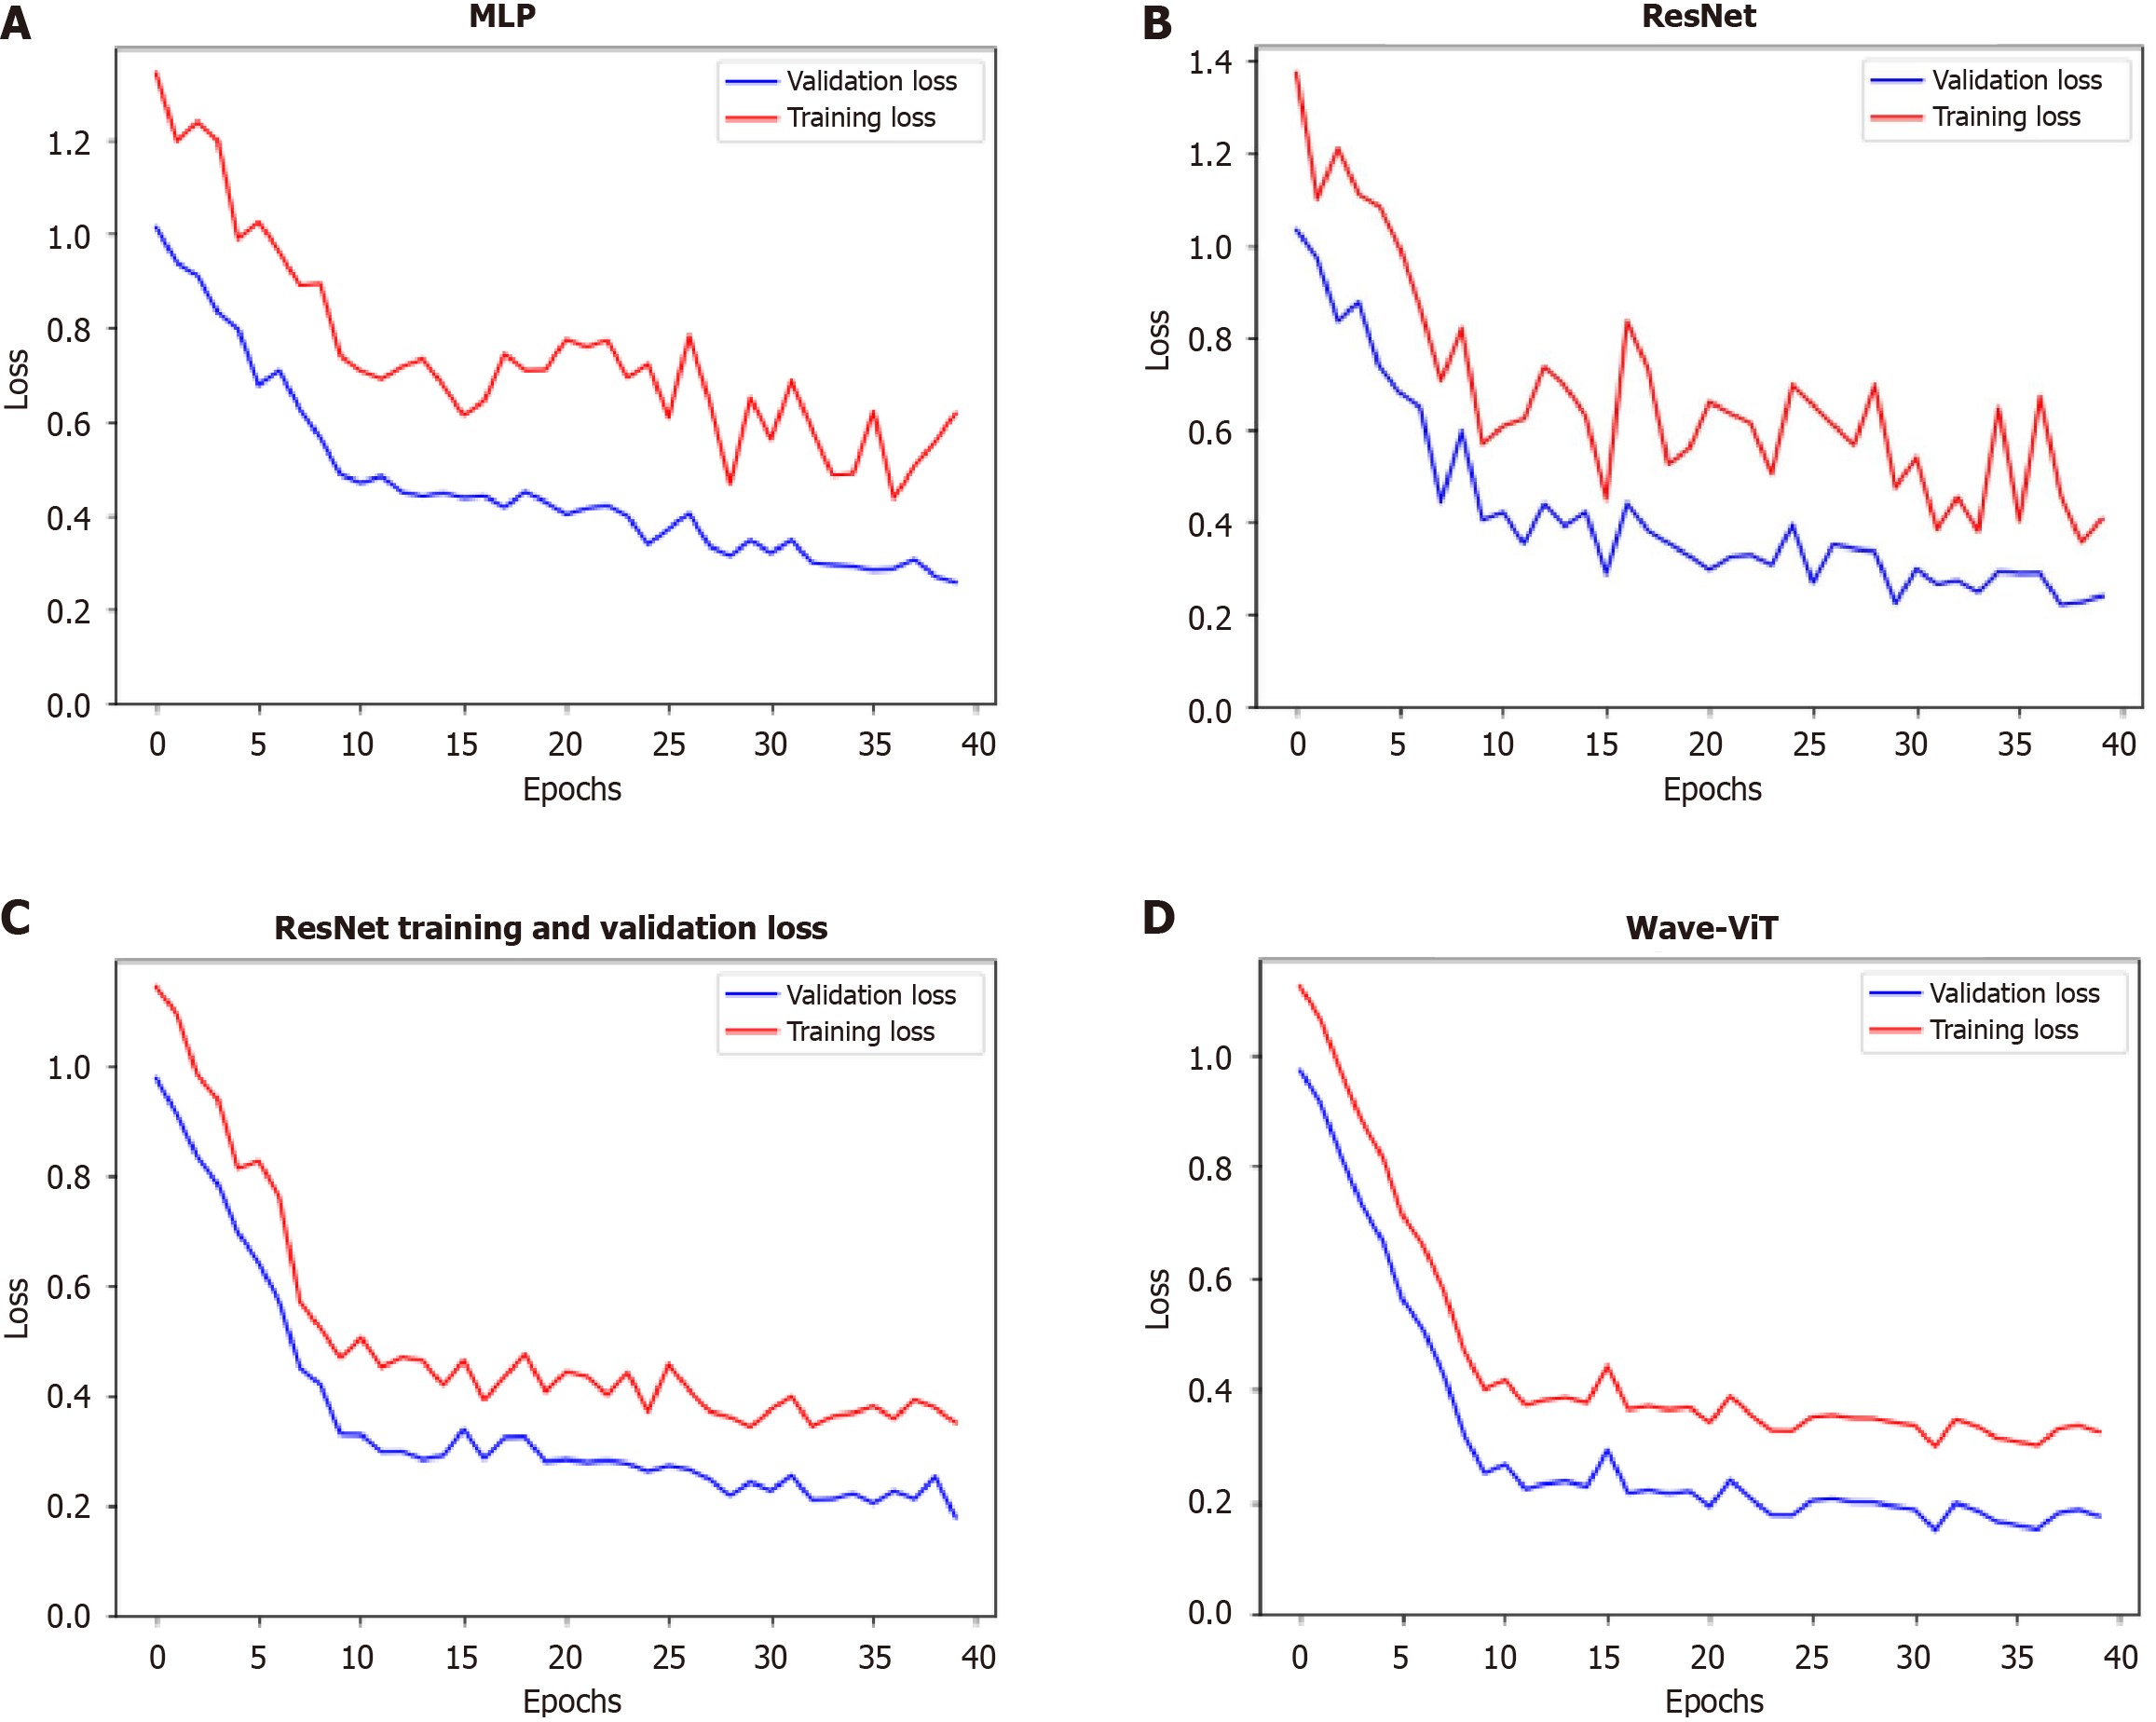

To further identify the optimal model, this study analyzes the variation in loss function values during training. The four models - MLP, ResNet, transformer, and Wave-ViT - show significant differences in their training performance, as reflected in the stability and final values of their loss functions, which follow a trend of progressive improvement and reduction, as shown in Figure 6. These differences stem from their unique network architectures and training strategies. The following analysis, based on Figure 6, will detail the distinctions among these models in terms of loss function stability and final loss values.

MLP is a basic deep learning model composed of multiple fully connected layers. During training, the loss function for MLP often exhibits significant fluctuations, especially in the early stages. This is due to the longer gradient propagation paths in MLP, which make it prone to gradient vanishing or explosion issues, resulting in unstable parameter updates and pronounced oscillations in the loss function. Furthermore, the MLP’s limited representational capacity makes it challenging to effectively learn complex data features, leading to slower loss convergence and a relatively high final loss value. Its loss function curve typically shows a jagged pattern with slow convergence and is prone to get trapped in local minima.

ResNet mitigates the gradient vanishing problem in deep neural networks by introducing skip connections, allowing gradients to bypass certain layers during backpropagation. This design makes the model easier to train and enables the training of deeper networks. During training, ResNet’s loss function shows greater stability than MLP, with significantly reduced fluctuations. This is due to the skip connections, which improve gradient propagation and stabilize parameter updates. Additionally, ResNet’s convolutional layers effectively capture local features in image data and, through stacking multiple convolutional layers, learn higher-level feature representations, enhancing the model’s expressive power. As a result, ResNet achieves lower final loss values and faster convergence than MLP. Its loss function curve is relatively smooth, converges more quickly, and is more likely to approach the global minimum.

The core of the transformer model is the self-attention mechanism, which captures relationships between any two elements in the input sequence, effectively learning long-range dependencies. Unlike MLP and ResNet, the transformer model processes all elements in the input sequence in parallel, resulting in faster training and the ability to handle longer sequences. During training, the transformer model’s loss function exhibits even greater stability than that of ResNet, with smaller fluctuations. This stability arises from the self-attention mechanism’s capacity to capture contextual information, leading to more stable parameter updates and better learning of global data features. Additionally, the transformer model’s strong representational ability enables it to learn more complex feature representations, resulting in lower loss values and faster convergence than ResNet. Its loss function curve is exceptionally smooth, converges very quickly, and typically achieves very low loss values.

Wave-ViT is a model that applies the transformer architecture in the frequency domain. It first transforms input data into the frequency domain and then utilizes the transformer model for feature extraction in this domain. This approach effectively captures frequency information in the data and leverages the transformer model’s parallel processing capability to enhance computational efficiency. During training, the loss function of Wave-ViT is even more stable than that of the transformer model, with minimal fluctuations. This is because frequency domain representation can effectively reduce noise and highlight essential features in the data, resulting in more stable parameter updates. Additionally, Wave-ViT excels in capturing global data features and effectively learns frequency-based information, leading to lower loss values and faster convergence than the transformer model. Its loss function curve is exceptionally smooth, with rapid convergence to very low loss values, and is less prone to getting trapped in local minima.

In summary, from the perspective of loss function variation, these four models exhibit a clear progression in stability and final loss values: MLP shows the most volatile loss function with large fluctuations and a high final loss value; ResNet is relatively stable with smaller fluctuations and a lower final loss value than MLP; the transformer model is even more stable, with minimal fluctuations and a lower final loss value than ResNet; and Wave-ViT demonstrates the highest stability, with minimal fluctuations and the lowest final loss value. This difference primarily stems from the unique architecture and training strategies of each model. MLP lacks effective mechanisms to address the vanishing gradient problem; ResNet alleviates this issue through skip connections; the transformer captures long-range dependencies through its self-attention mechanism; and Wave-ViT combines the benefits of frequency domain representation and the transformer model, further enhancing model stability and representational capacity. This increased stability directly translates into better generalization and robustness, with Wave-ViT often showing optimal performance on the test set. Naturally, actual outcomes may be influenced by factors such as datasets and hyperparameters, but the overall trend follows this pattern.